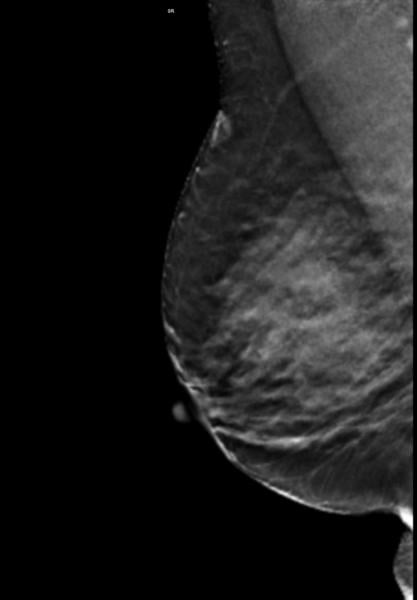

(This article was updated in July 2016) There has been much talk in the news lately about mammographic breast density ...